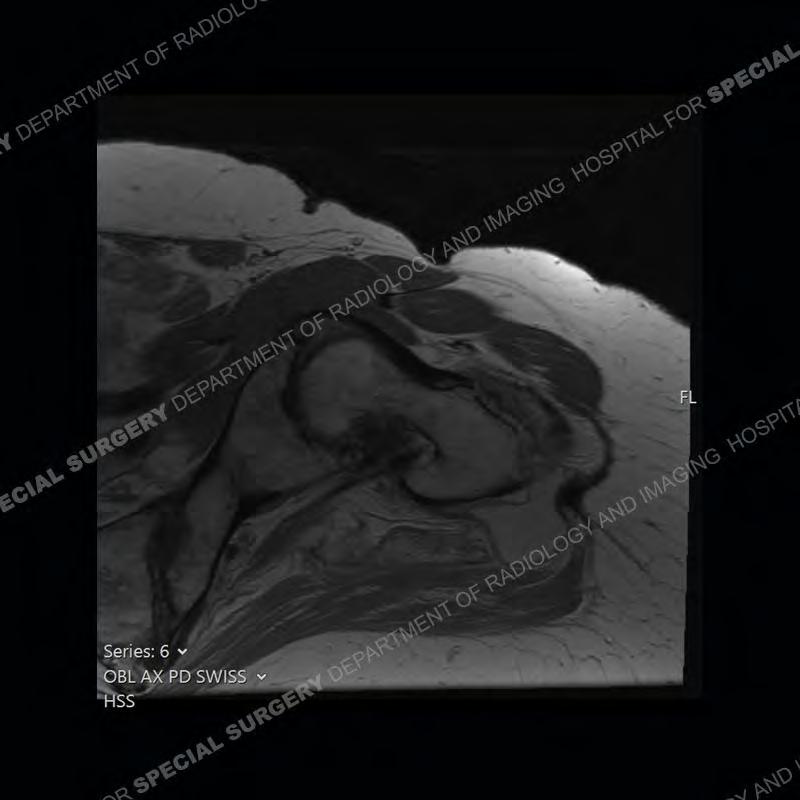

The radiograph is not particularly contributory in this case. The MRI demonstrates markedly abnormal architecture of the gluteus minimus and anterolateral band of the gluteus medius. Portions of the tendons are high signal, portions are highly attenuated, and portions are disrupted. A large, complex fluid collection is present in the adjacent soft tissue.

Diagnosis: Gluteal Tendinosis and Disruption with Complex Trochanteric Bursal Collection

Not as much of a diagnostic dilemma as many of the other cases shown but just a nice example of the pathology seen of the gluteal tendons and a cause of trochanteric pain. Although, frequently thought of in isolation, trochanteric bursitis or bursal thickening is much more commonly a reactive change to underlying pathology of the subjacent gluteal tendons. The gluteus medius is divided into a posterior band and an anterolateral band. Tendinosis and partial tearing very commonly will involve the gluteus minimus and especially the more posterior fibers and then propagate into the anterior lateral band of the gluteus medius. Involvement of the posterior band of the medius is much less common and engenders a marked degree of functional impairment.